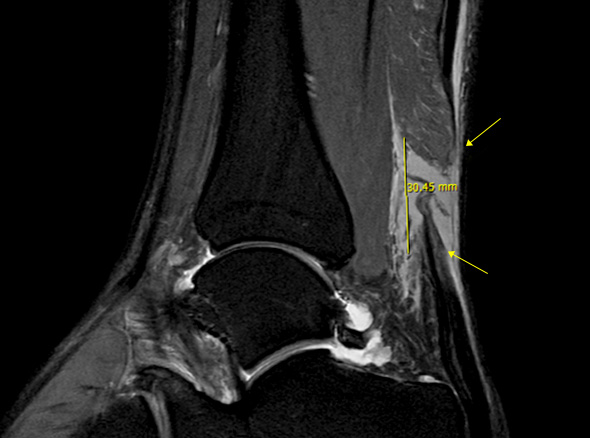

발뒤꿈치 뼈와 종아리 근육을 연결하는 아킬레스건이 부분적으로 또는 완전히 찢어지는 손상입니다.

아킬레스건은 우리 몸에서 가장 크고 강력한 힘줄 중 하나로, 걷기, 뛰기, 점프 등의 동작을 수행하는 데 중요한 역할을 합니다.

* 환자에게 받은 소중한 자료입니다.